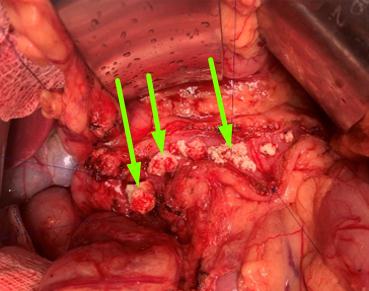

Trường hợp thứ 2: bệnh nhân P.T.N nam 38 tuổi, cũng có thói quen sử dụng rượu sớm từ năm 16 tuổi kèm theo hút thuốc lá mỗi ngày trung bình 1 bao. Cách vào viện một tháng, anh N xuất hiện đau bụng vùng thượng vị âm ỉ kèm theo vàng mắt, vàng da tăng dần, gầy sút 5 kg trong vòng 1 tháng. Anh N đi khám và điều trị tại nhiều bệnh viện lớn ở Hà Nội và được chẩn đoán là tắc mật do viêm tụy mạn. Sau một thời gian điều trị nội khoa nhưng tình trạng bệnh không tiến triển, gia đình tìm hiểu thông tin và đã đến phòng khám Khoa Phẫu thuật tiêu hóa – Gan mật tụy. Người bệnh P.T.N vào viện với thể trạng gầy, da niêm mạc vàng đậm, đau nhiều thượng vị lan sau lưng, ăn uống kém. Trên cộng hưởng từ và cắt lớp vi tính cùng với siêu âm nội soi (2 lần) đều cho thấy có hình ảnh giãn ống tụy, sỏi tụy, giãn đường mật trong và ngoài gan, không rõ khối vùng đầu tụy. Xét nghiệm sinh hóa và miễn dịch cho thấy Bilirubin toàn phần tăng cao 268 μmol/l, các chất chỉ điểm u (CEA và CA 199) trong giới hạn bình thường. Sau khi làm đầy đủ các thăm dò chúng tôi quyết định phẫu thuật cho người bệnh với chẩn đoán: tắc mật do viêm tụy mạn, sỏi tụy, theo dõi u đầu tụy, dự kiến phẫu thuật Frey-Beger hoặc phẫu thuật cắt khối tá tụy nếu trên sinh thiết tức thì tổ chức tụy trong mổ có tế bào ác tính. Thăm dò trong mổ thấy toàn bộ đầu – thân – đuôi tụy cứng chắc, đầu tụy to thâm nhiễm mạc treo ĐT ngang. Sinh thiết tức thì hạch quanh đầu tụy cho kết quả là ung thư biểu mô tuyến di căn, do đó bệnh nhân được quyết định cắt khối tá tràng – đầu tụy, nạo vét hạch mở rộng. Kết quả giải phẫu bệnh khối tá tụy và tổ chức hạch quanh tụy là ung thư biểu mô tuyến tụy trên nền viêm tụy mạn tính, di căn 34 trên 78 hạch nạo vét được. Sau mổ, người bệnh được sử dụng hệ thống giảm đau đa mô thức, vận động hồi phục sớm và được điều trị phối hợp với các chuyên khoa dinh dưỡng, nội tiết. Bệnh nhân ổn định và ra viện ngày thứ 9 sau mổ và được hẹn khám lại để xét điều trị bổ trợ. Tuy phẫu thuật thành công nhưng tiên lượng trường hợp này sẽ rất nặng do tụy viêm đã ung thư hóa và di căn hạch.

A. Hình ảnh sỏi tụy trên CLVT

B. Hình ảnh sau cắt bỏ khối tá tụy |

C. Khối tá tụy |

Hình 4: Ảnh trên cắt lớp vi tính, trong và sau mổ của bệnh nhân P.T.N